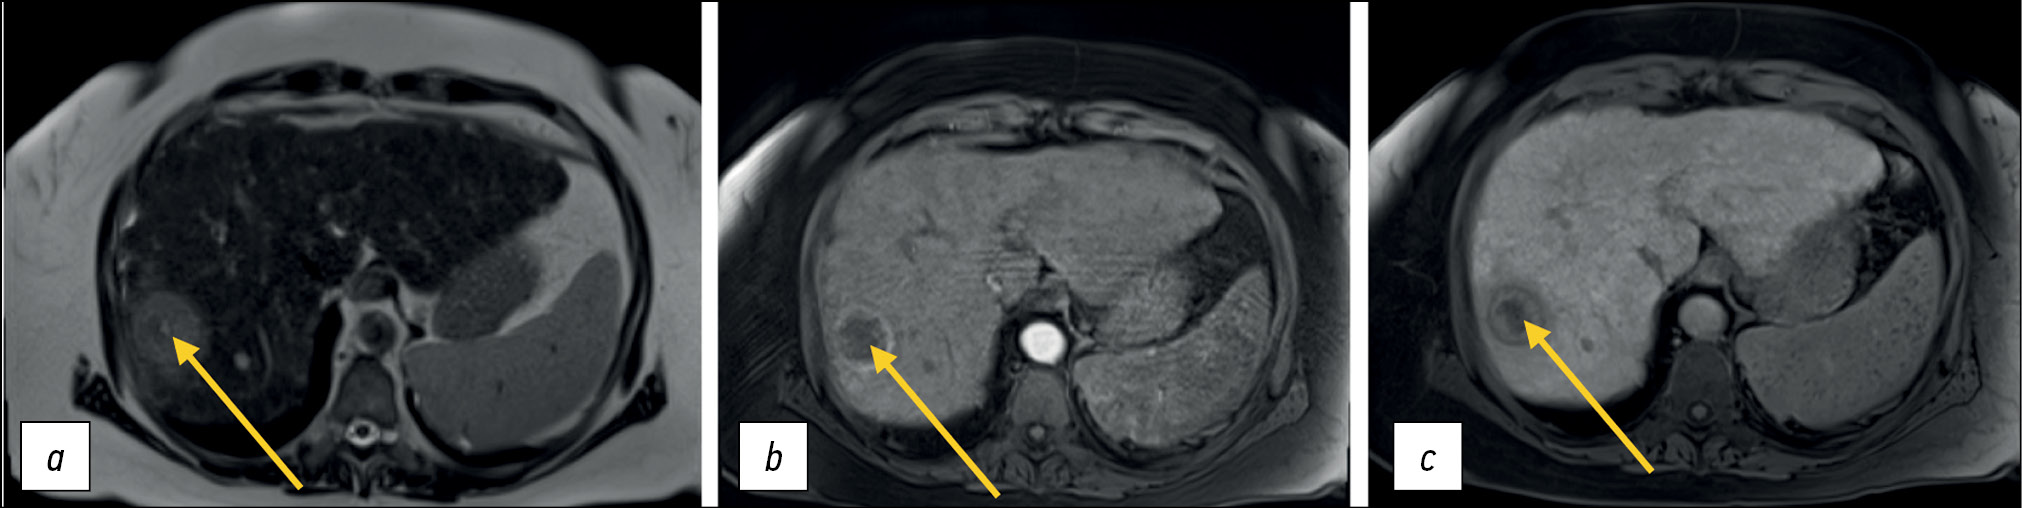

Another important aspect of T1-WIs is the use of intravenous contrast enhancement, including hepatospecific contrast agents. For example, gadoxetic acid has a high affinity for hepatocytes and thus allows for better visualization of liver pathologies (Fig. 1).

Figure 1. Liver magnetic resonance imaging with a hepatospecific contrast agent. A hepatocellular carcinoma nodule (arrows): a T2-weighted image: a hyperintense nodule is visualized; b Т1-weighted image, arterial phase: a ring-like contrast uptake is visualized; c Т1-weighted image, hepatospecific phase, 20 min after contrast agent injection.

Contrast agents shorten the T1 relaxation time, resulting in higher signal intensity on T1-WIs. Depending on the blood supply to focal or diffuse lesions in parenchymal organs, various contrasting patterns are distinguished, which in general differ from those in adjacent unaffected tissues. Arterial phase imaging is accomplished by short sequences immediately after the administration of gadolinium-based contrast agents.